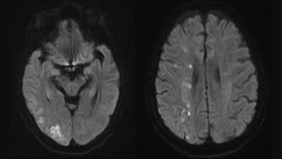

Hyperacute Hyperperfusion in ICAD stenting

By Chowdam Venkata Sai TEJA

Published on December 11, 2025